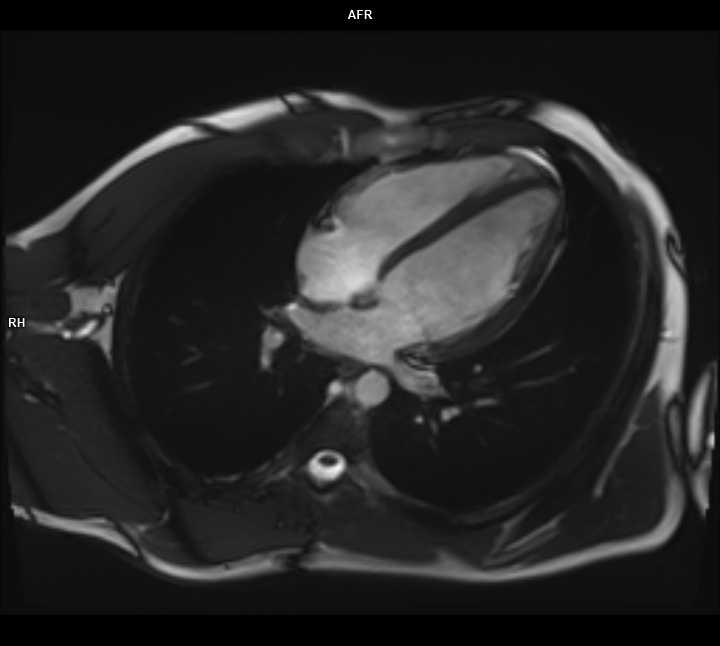

• 3 TESLA MR ÇEKİM GÖRÜNTÜLERİ

3 Tesla MR Çekim Görüntüleri

• 3 Tesla MR Çekim Görüntüleri